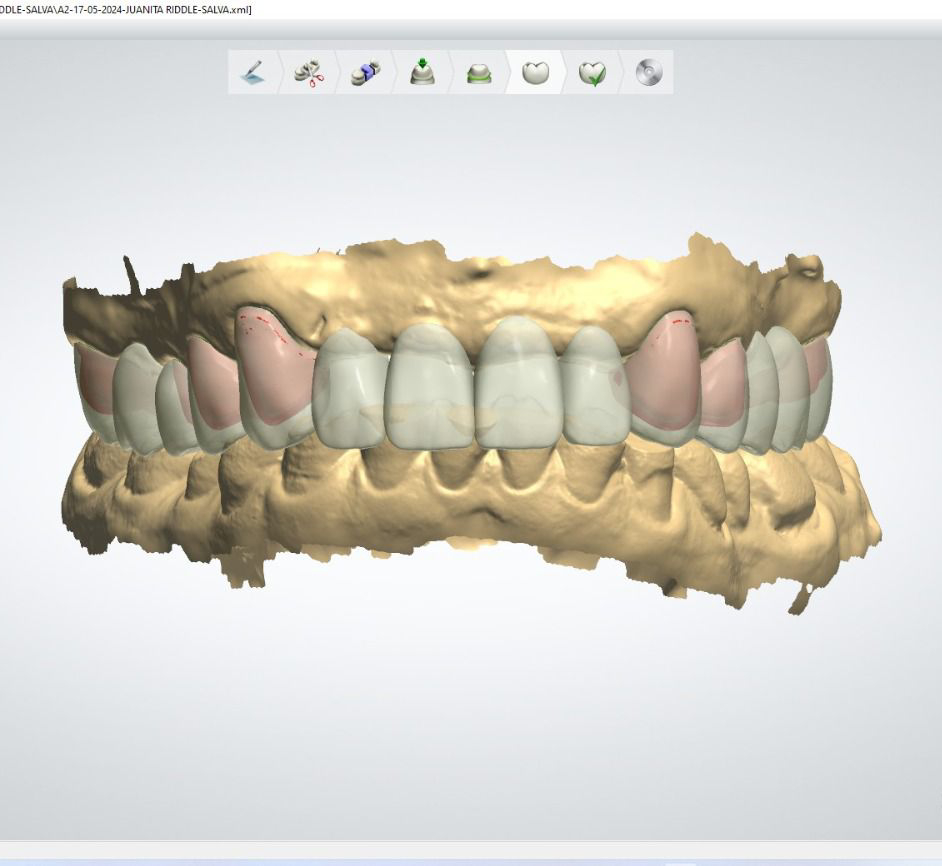

Casos de éxito

Estos son algunos de nuestros casos de éxito, mostrando el antes y después de nuestras intervenciones.

Rehabilitación superior e inferior con zirconia monolítico multicapa en color B1.